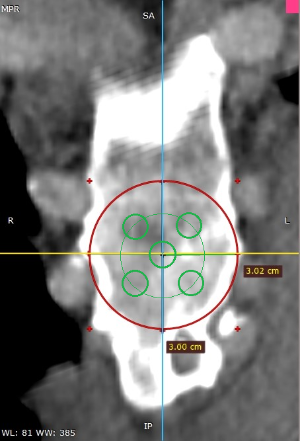

Los datos médicos del paciente, más la exploración clínica realizada por el equipo de cirugía, junto a un análisis pormenorizado de las imágenes del TAC y las reconstrucciones digitales en 3D de cada tórax realizadas conjuntamente con el equipo de ingenieros de Ventura Medical Technologies, son la base para determinar si la técnica Pectus Up está indicada y como se debe proceder en cada uno de los pacientes.

Con estos datos se selecciona el implante que mejor se ajustar a la anatomía de cada tórax, la ubicación exacta del sistema de elevación y, a su vez, proporciona al equipo quirúrgico un detalle de los pasos a tener en cuenta para llevar a cabo una correcta implantación.

Pectus Excavatum Pectus Excavatum Asimétrico Índice de Asimetría 0.6 (+R/-L)(|AI|> 0.05 Asimétrico) Índice de Haller 4.5 (HI >3.5) Índice de Corrección 49.13% Rotación esternal 18.1 ° (a la derecha)

Informe de evaluación del TAC de un paciente enviada al cirujano